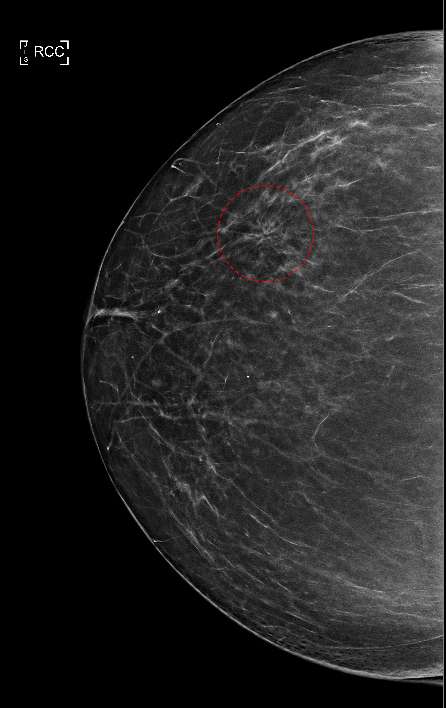

Craniocaudal mammogram view showing an architectural distortion within the lateral right breast (red circle). Note the irregular radiating lines from a central focal region compared to the surrounding normal breast parenchyma.

Figure 1: Craniocaudal mammogram view showing an architectural distortion within the lateral right breast (red circle). Note the irregular radiating lines from a central focal region compared to the surrounding normal breast parenchyma.

Figure 1 shows a classic mammogram appearance of architectural distortion. As denoted by the red circle, abnormal, fine tissue lines can be seen emanating in a radial pattern and appear to originate from a central focal region. This is in contrast to the surrounding normal parenchymal breast tissue which does not follow this irregular radial pattern. Architectural distortions may be present with no additional mammogram findings (as seen in Figure 1) or in association with other findings such as calcifications or dense masses.